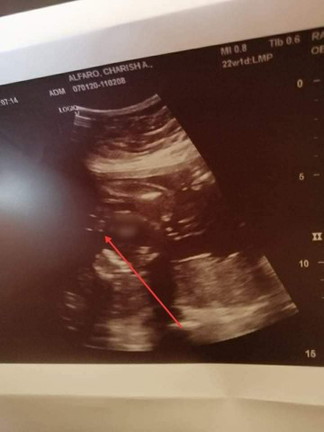

Ano po tingin nyo? girl or boy?

ANO PO SA TINGIN NYO? GULONG GULO NA PO AKO MGA SIS. GUSTO KO NA BUMILI NG DAMIT NI BABY, SABI UNA ULTRASOUND GIRL TAPOS NGAYON BOY NAMAN DAW. NAG HANAP PA AKO SA GOOGLE NG MGA ULTRASOUND NG GIRL AND BOY PINAG COCOMPARE KO KASI WALA NAMAN LAWIT NA NAKITA.

Parang boy parang lawit. Hindi ako sure sis

Girl ?kase parang hamburger eh

boy po yan